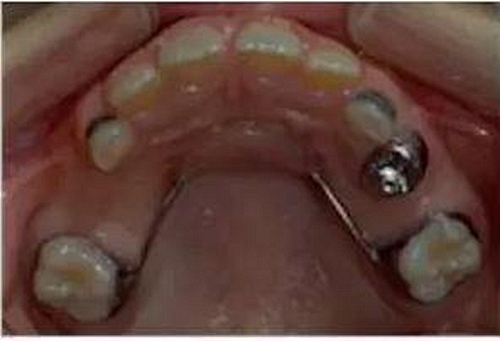

③Nance弓(腭弓)式間隙保持器

乳牙缺失致恒牙“亂長(zhǎng)”,這個(gè)“間隙保持器”可預(yù)防

Nance弓式間隙保持器,也稱為腭弓式間隙保持器,是用于上牙需要間隙保持的部位,它和舌弓式間隙保持器是相對(duì)應(yīng)的。